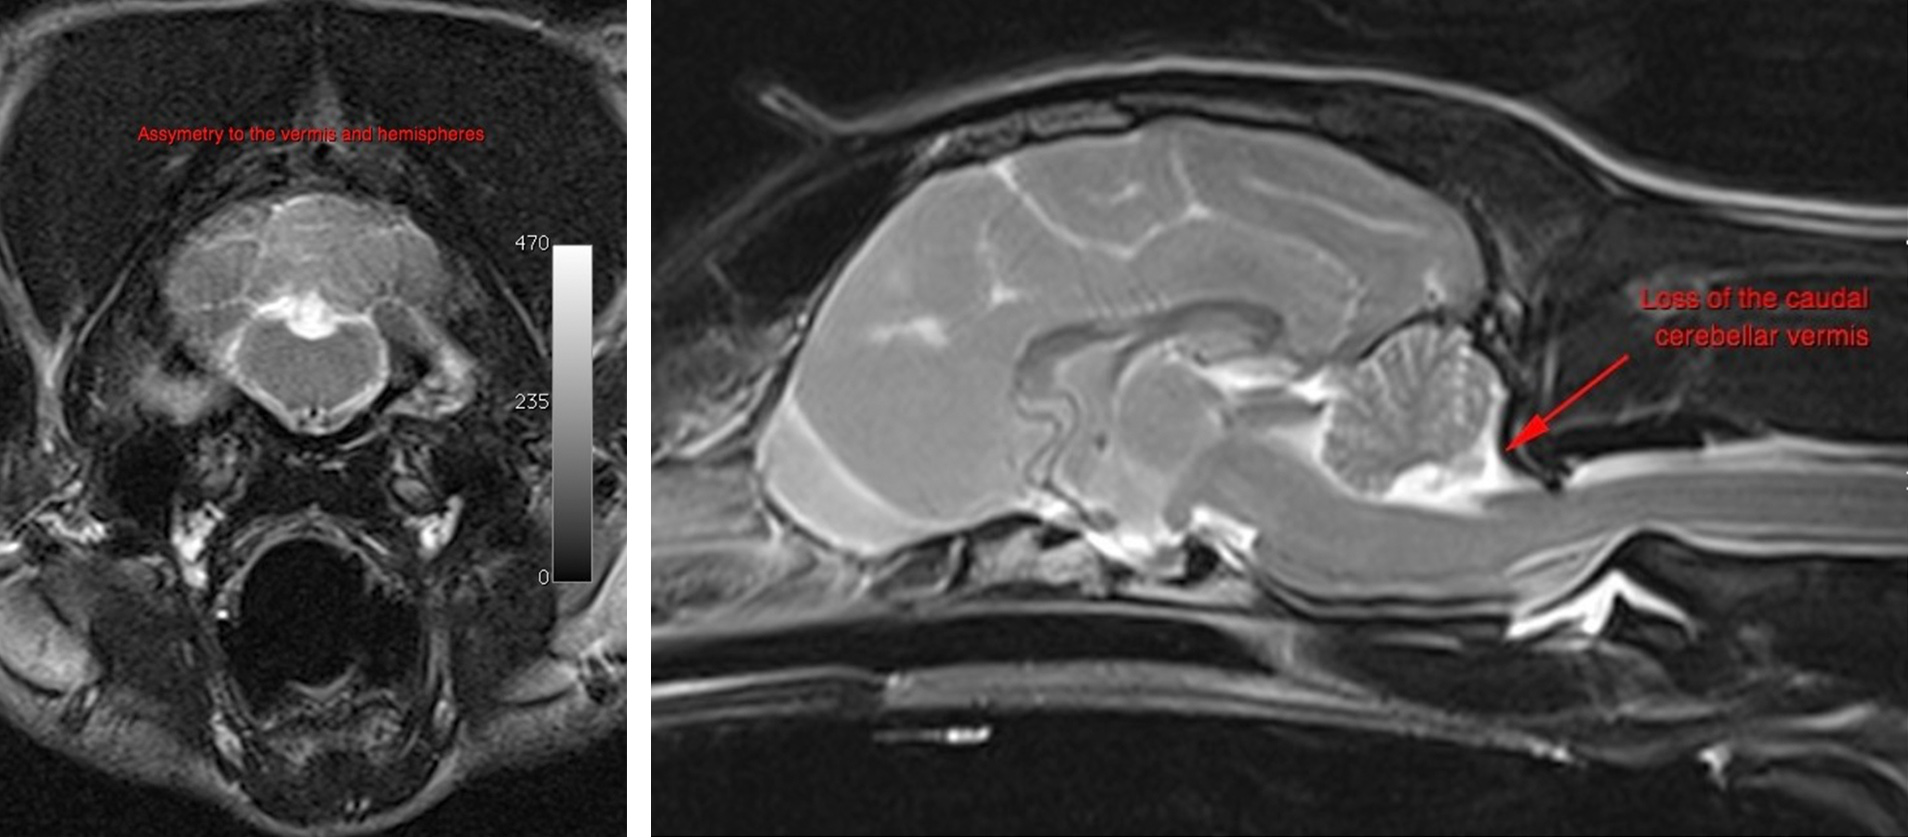

In case it’s not clear, it’s a photo of a dog, with a little bit of her brain missing, bless her!